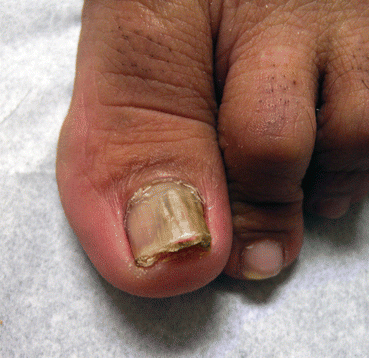

Distal subungual onychomycosis is primarily a nail bed disorder. Infection usually begins with involvement of the distal part of the nail bed and progresses proximally along the ventral surface of the nail plate. It most commonly affects the great toe [7]. The nails become thick due to subungual hyperkeratosis, which is associated with onycholysis. The onycholytic nail plate is yellowish white to brown in color (Fig. 7.4). Agents responsible for distal subungual onychomycosis include Acremonium spp., Fusarium spp., and Alternaria spp. [5, 7, 8]. Periungual inflammation may be seen in distal subungual onychomycosis caused by Fusarium spp. [5]. Tinea pedis is not commonly associated with mold onychomycosis, although it can be seen in Scopulariopsis brevicaulis infections.

Fig. 7.4

Distal subungual onychomycosis from molds